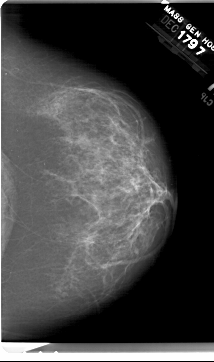

A_1518_1.RIGHT_MLO

RIGHT_MLO LINES 6541 PIXELS_PER_LINE 3811 BITS_PER_PIXEL 12 RESOLUTION 43.5 NON_OVERLAY